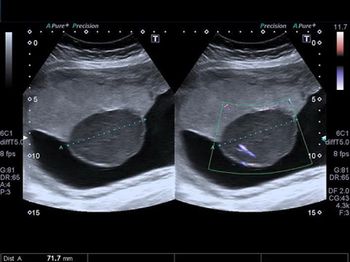

What abnormality of the placenta is affecting this late second-trimester pregnancy?